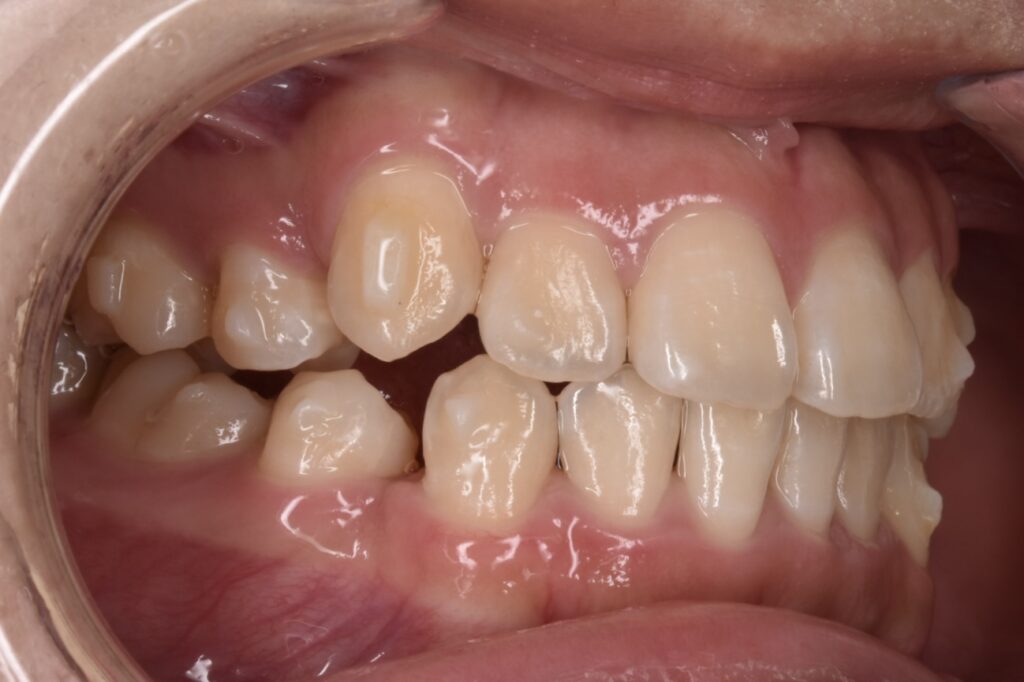

10代女性 以前より八重歯をなくしたいと悩んでいて、高校卒業と同時に矯正を始めたいと、ご家族でご相談にご来院くださいました。

Before

現在矯正開始から38週経過し38枚目になっています。追加アライナーなし、順調に経過しています。八重歯感もだいぶ改善してきましたね。噛み合わせは本人様は全然気にならない様ですが最後に調整していきます。追加アライナーとゴムかけなどです。